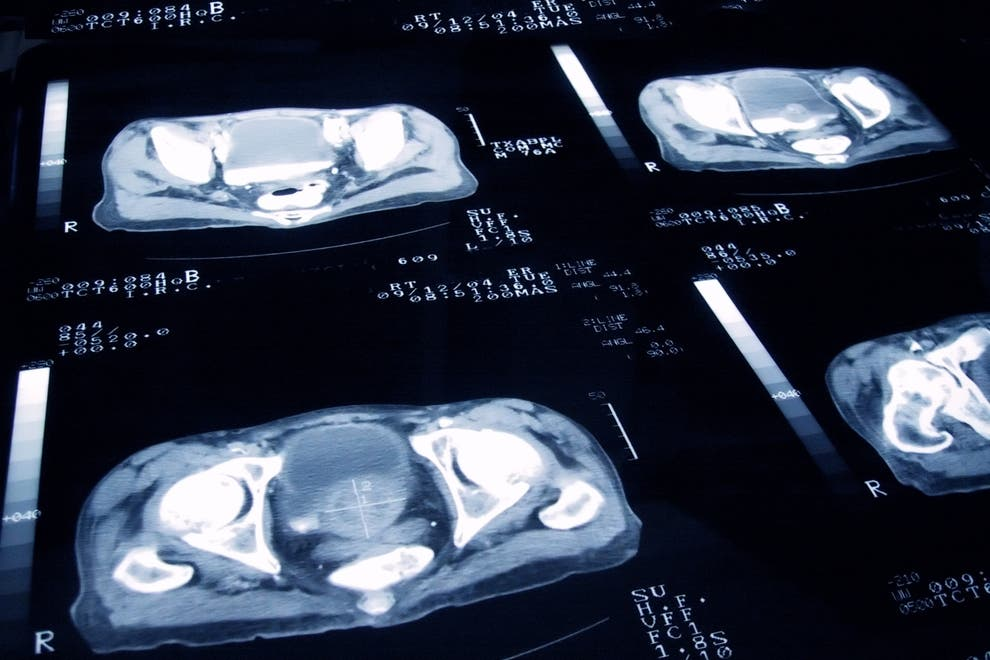

Tecnologia a serviço do bem. Uma inteligência artificial (IA) foi capaz de revelar uma nova forma agressiva de câncer de próstata. A descoberta revoluciona a forma como a doença é diagnosticada e tratada.

Usando IA para analisar dados de DNA, os pesquisadores identificaram dois subtipos do câncer de próstata. Em última fase, o estudo leva a tratamentos personalizados para cada paciente individualmente.

No estudo, os pesquisadores usaram IA para estudar alterações no DNA de amostras de câncer de próstata de 159 pacientes.

O resultado identificou dois grupos distintos de câncer.